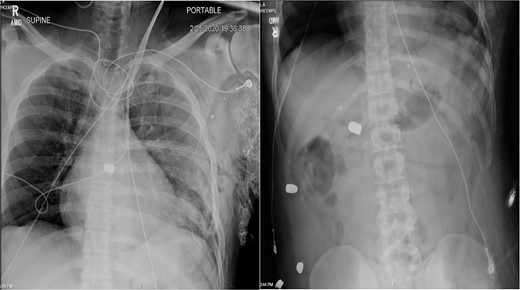

In the OR, exploratory laparotomy, right nephrectomy, liver packing, and pericardial window were performed. The pericardial window was negative for blood. With no suspected cardiac injury, intraoperative fluoroscopy (Fig. 1) and transesophageal echocardiogram (TEE) (Fig. 2) were used to locate the bullet. It was suspected to be intravascular secondary to venous embolism from the retro-hepatic inferior vena cava (IVC). Cardiothoracic surgery was consulted for removal of the bullet. With abdominal hemorrhage controlled, the surgeons agreed the patient was an acceptable risk for anticoagulation and cardiopulmonary bypass. Sternotomy was performed, the patient was placed on cardiopulmonary bypass, and the bullet was removed through a right atriotomy.

Intraoperative fluoroscopy demonstrating bullet in the right ventricle.

Case 1 involved a stable patient with a single GSW to the left back and a retained bullet over the right ventricle. The trauma team identified the bullet overlying the cardiac silhouette and performed a CT scan to determine its trajectory. The scatter artifact complicated localization, but a pericardial window excluded cardiac injury. Intraoperative imaging (fluoroscopy and TEE) revealed a venous bullet embolism from the retro-hepatic IVC to the right ventricle. The bullet was mobile on fluoroscopy, and TEE provided the best imaging. The trauma and cardiothoracic surgeons discussed bullet removal timing, considering the patient’s stability and heparinization needs. They opted for immediate removal due to the potential lethality of pulmonary artery embolism. The operation was successful, requiring only one surgery for definitive management. This case highlights the success of immediate bullet removal in hemodynamically stable, asymptomatic patients with venous embolism.